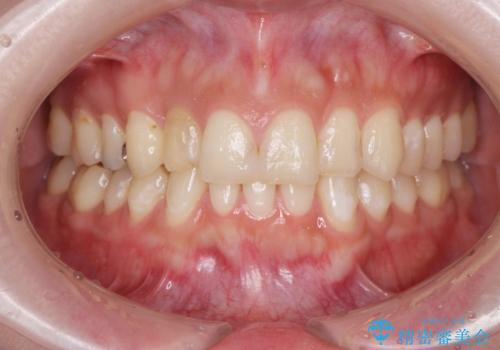

充填物の変色を繰り返す前歯のセラミック治療

- 神経をとった前歯の変色や、前歯の充填物の変色が大きくなってきたので審美性の改善を求めて来院されました。

充填物や充填物下に再発した虫歯を丁寧に除去し、セラミッククラウンによる審美性の改善、虫歯治療を計画します。

- 52.8万円(ジルコニアクラウン×4・仮歯×4)費用は治療当時の料金となります

ある程度の大きさになった充填物は、劣化の少ないセラミッククラウンにすることで色調の劣化を抑え、審美性を保つことができます。